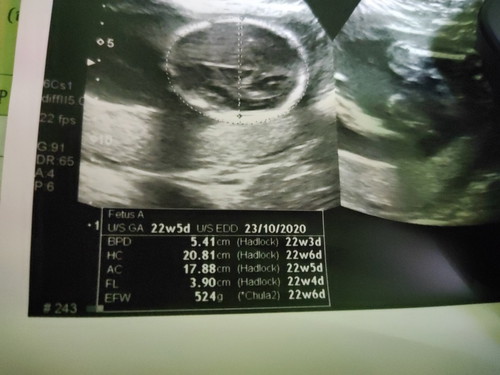

อยากทราบว่าครั้งแรกที่ได้ซาวด์แล้วหมอบอกว่า กำหนดคลอดวันที่ 3/11/63 แต่พอซาวด์ครั้งที่2 ได้เห็นในใบซาวด์ว่ากำหนดหนดคลอดวันที่ 23/10/63 ที่นี้อยากรู้ว่าเราควรเชื่อในใบซาวด์ครั้งที่2 ดีมั้ยค่ะ